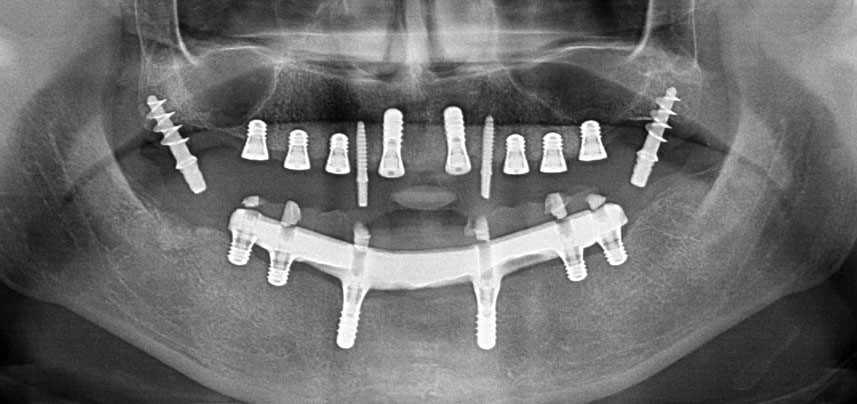

Implantatgetragene festsitzende Prothesen verbessern bei zahnlosen Patienten Kaufunktion und Lebensqualität. Infolge von Knochenresorption und umfassender Pneumatisation der Nebenhöhlen verfügte eine Patientin nur über eine minimale Knochenhöhe im Seitenzahnbereich des Oberkiefers. Die Implantatlager wurden mit einem piezochirurgischen Gerät und einem neuen Set spezieller Instrumente präpariert. Es wurden zwei 10-mm und sechs 4-mm-Implantate inseriert, die zur Abstützung einer steggetragenen und verschraubten CAD/CAM-Versorgung dienten.

Eine 41-jährige Patientin ohne systemische Besonderheiten hatte aufgrund von Parodontitis und Karies alle Zähne verloren. Zuletzt musste sie im Ober- und Unterkiefer schleimhautgetragene Totalprothesen tragen, was wegen deren schlechter Passung große Probleme beim Kauen verursachte. Die Patientin entschied sich, Implantate für eine steggetragene CAD/CAM-Prothese im Unterkiefer setzen zu lassen.

Drei Jahre später war es Zeit für eine gleichartige Oberkieferprothese. Basierend auf der DVT-Planung wurde durch Verwendung kurzer Implantate eine Sinusaugmentation vermieden und die geplanten Implantatpositionen wurden mit einer Bohrschablone auf den Kieferkamm übertragen (Abb. 1 und 2).

Wegen des relativ harten Knochens (D2) an den Positionen 11 und 21 wurden die 10 mm langen Implantatlager in diesem Bereich abschließend mit einem 4-mm-Spiralbohrer, dem chirurgischen Winkelstück WS-75 L von W&H und dem W&H Implantmed Implantologiemotor in Verbindung mit dem optionalen W&H Osstell ISQ module präpariert. Im Gegensatz dazu wurde der weiche Knochen der Implantatlager im Seitenzahnbereich mit dem Piezomed I3P auf den abschließenden Durchmesser von 3 mm erweitert. Die Implantate wurden dann transgingival eingesetzt, die Einheildauer betrug drei Monate (Abb. 6-10). Die vorhandene Prothese wurde auf vier provisorischen Implantaten abgestützt (Abb. 8).